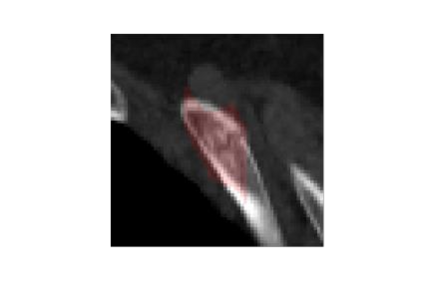

Rib fractures are a common and potentially severe injury that can be challenging and labor-intensive to detect in CT scans. While there have been efforts to address this field, the lack of large-scale annotated datasets and evaluation benchmarks has hindered the development and validation of deep learning algorithms. To address this issue, the RibFrac Challenge was introduced, providing a benchmark dataset of over 5,000 rib fractures from 660 CT scans, with voxel-level instance mask annotations and diagnosis labels for four clinical categories (buckle, nondisplaced, displaced, or segmental). The challenge includes two tracks: a detection (instance segmentation) track evaluated by an FROC-style metric and a classification track evaluated by an F1-style metric. During the MICCAI 2020 challenge period, 243 results were evaluated, and seven teams were invited to participate in the challenge summary. The analysis revealed that several top rib fracture detection solutions achieved performance comparable or even better than human experts. Nevertheless, the current rib fracture classification solutions are hardly clinically applicable, which can be an interesting area in the future. As an active benchmark and research resource, the data and online evaluation of the RibFrac Challenge are available at the challenge website. As an independent contribution, we have also extended our previous internal baseline by incorporating recent advancements in large-scale pretrained networks and point-based rib segmentation techniques. The resulting FracNet+ demonstrates competitive performance in rib fracture detection, which lays a foundation for further research and development in AI-assisted rib fracture detection and diagnosis.